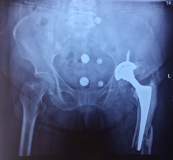

病例2 患者譚某,女性,79歲,左髖關(guān)節(jié)行置換手術(shù)14年,行翻修手術(shù)8年,兩小時(shí)前摔傷致左髖關(guān)節(jié)翻修術(shù)后假體周圍骨折,到我院住院治療,專家團(tuán)隊(duì)討論后,決定進(jìn)行二次翻修手術(shù),二次翻修相比第一次翻修,手術(shù)難度更大,面臨的困難更多,經(jīng)過精心的術(shù)前設(shè)計(jì),周密的術(shù)前準(zhǔn)備,手術(shù)過程順利,術(shù)后效果良好。

術(shù)前X線片

術(shù)后X線片